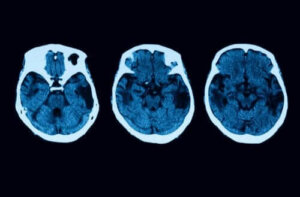

- Зародження деменції. Варто зауважити, що у хворих на церебральну атрофію досить часто спостерігаються такі розлади, як гіпометаболізм та гіпоперфузія. Їх можна визначити з допомогою спеціальних досліджень, що передбачають сканування організму з допомогою нейровізуалізації. Утім, не забувайте, що деменція виникає на відносно пізніх стадіях захворювання.

Утім, на цьому процес діагностики не завершиться. Для того, щоб розвіяти будь-які сумніви, лікар може призначити інші неврологічні дослідження, зокрема МРТ та інші види томографії. Якщо діагноз “атрофія головного мозку” підтвердиться, спеціалісти запропонують вам кілька видів терапії.